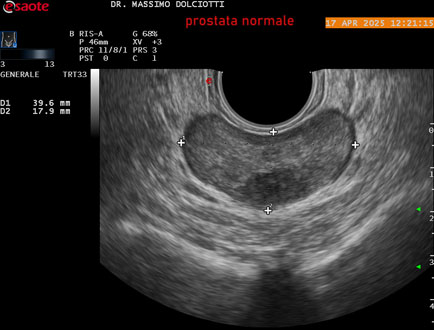

Data inserimento: 01/10/2025

Ecografia del: 17/04/2025

Strumento: Esaote MyLab Eight

Sonda: Convex Multifrequenza 1-8 MHz, Endocavitaria Multifrequenza 3-9 MHz e 3-13 MHz

Età Paziente: M 35 anni

Motivazione dell'esame: disuria.

Commento all'esame: le immagini ed il video documentano la prostata di ecostruttura regolare e morfovolumetria normale con diametro trasversale di 40 mm, diametro anteroposteriore di 21 mm e diametro longitudinale di 43 mm, con volume prostatico calcolato di 18 cc (v.n. < 20 cc), il profilo prostatico è regolare e netto, non si documentano calcificazioni intraghiandolari, la vascolarizzazione della ghiandola è normale. La vescicola seminale destra presenta diametro longitudinale di 44,4 x 7,8 mm, la vescicale seminale sinistra ha diametro longitudinale di 45,3 mm x 7,2 mm.

Conclusioni: prostata normale (normal prostate).

Presentazione: Dr. Massimo Dolciotti - Ancona

Elaborazione digitale: Andrea Dini - Ancona

VISUALIZZA IL VIDEO